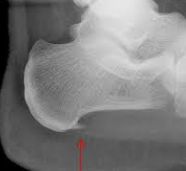

X線像はまた定型的で特徴がある。

骨は石灰質に乏しいため、その陰影が淡く、海綿質および皮質の境界が正常より不鮮明であって、骨梁網が粗にみえる。

また病機のさかんな時期には長管骨の骨端軟骨線が幅広く、とくにその中心が広いため、骨幹端は盃状に拡大し、骨端は扁平になる。

治癒に向かった場合は骨端軟骨線は狭小となり、骨幹端の盃状は軽度になって帯状を呈し、陰影は濃化します。